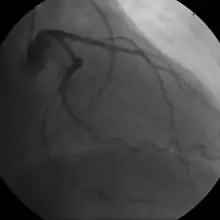

- Coronary angiography